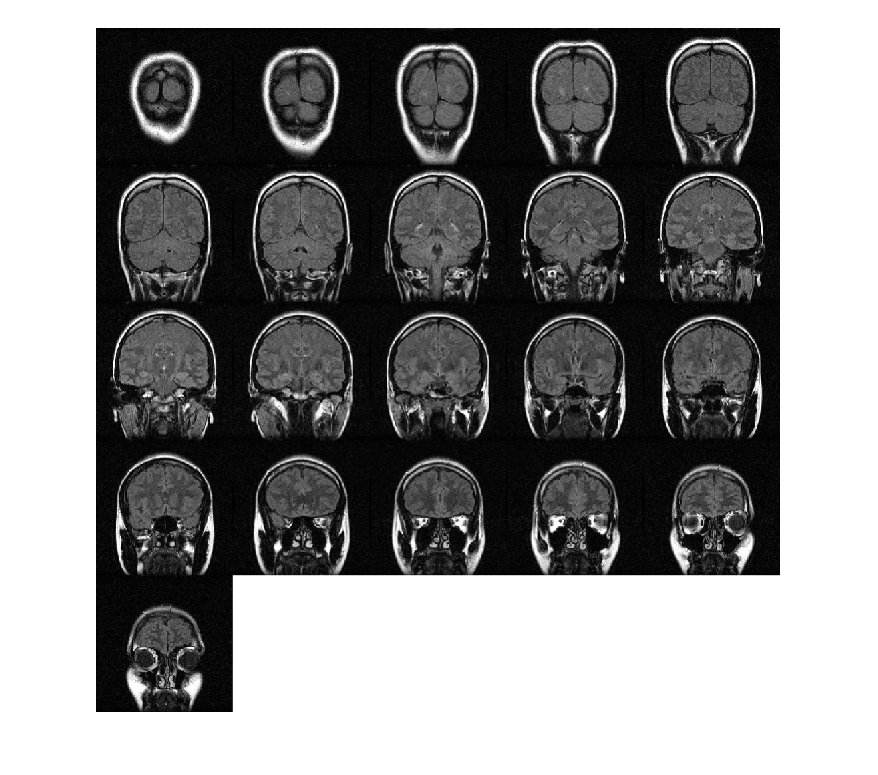

Создайте 3-D эллипсоидальный фильтр. Задайте длину полуоси 7 пикселей в направлениях y (строки) и x (столбцы), и длину полуоси 3 пикселя в направлении z (плоскости).

H = fspecial3('ellipsoid',[7 7 3]);

Сглаживайте объем фильтром.

volSmooth = imfilter(mristack,H,'replicate');

Отображение плоскостей сглаженного объема.

montage(volSmooth,'BackgroundColor','w')

Figure contains an axes. The axes contains an object of type image.